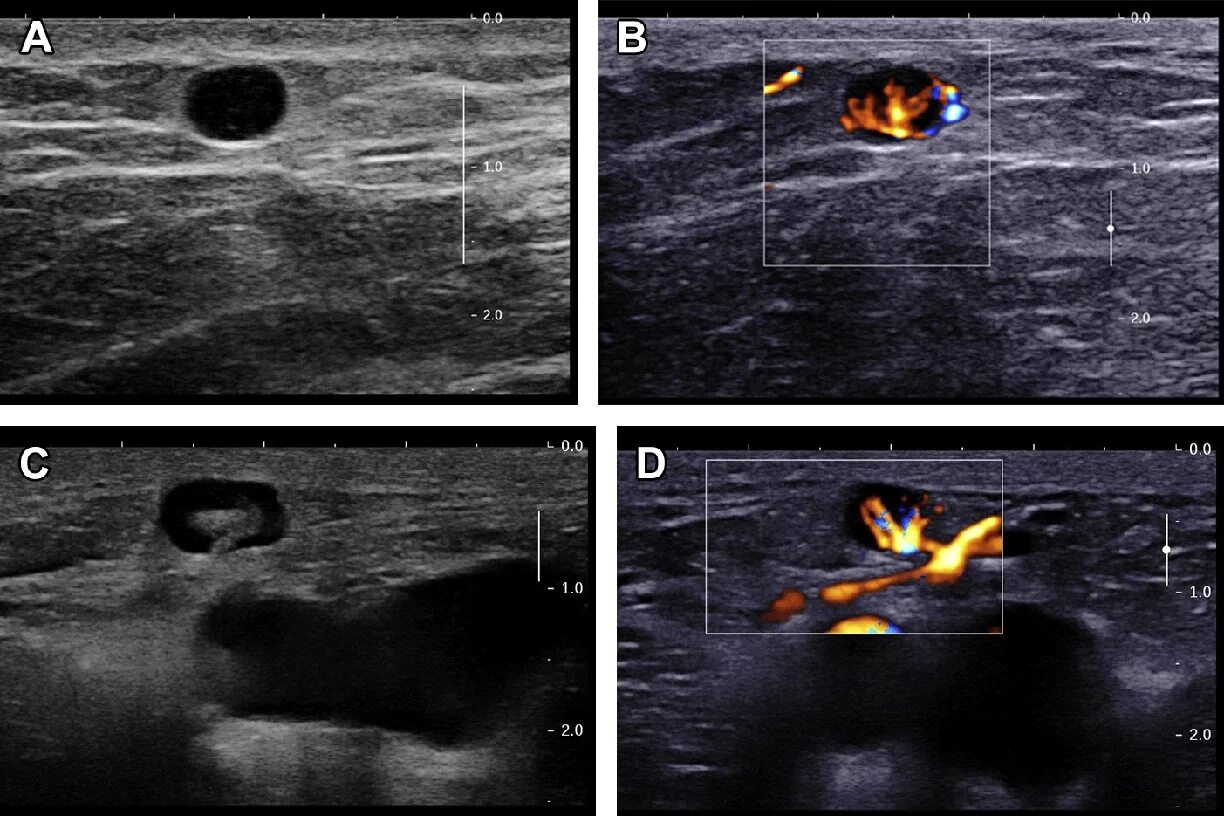

Лучевая терапия метастазов в лимфоузлах